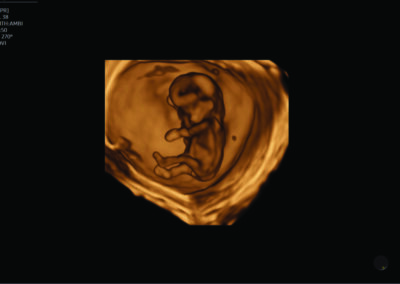

Comprehensive, advanced and expert MFM care for high-risk pregnancies

- Fetal anomalies